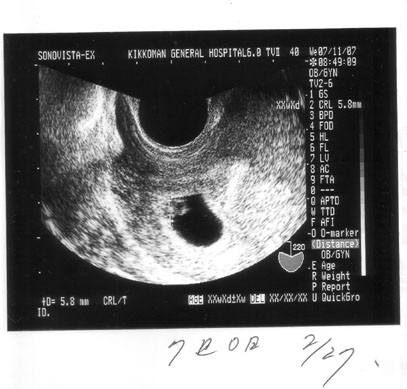

a.jpg2回目に撮ったエコーです。1度目は卵できてなかったw

よくわからないかな?

真ん中の袋の端にあうのが卵。

大きさは5.8㍉